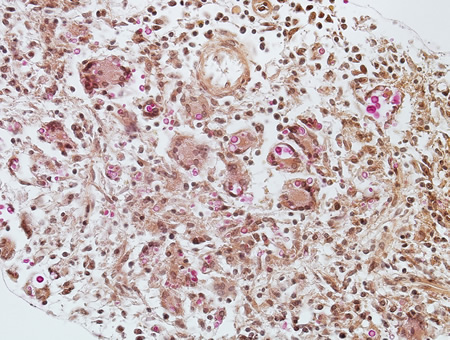

Biópsia de paciente com vírus da imunodeficiência humana (HIV) com toxoplasmose, com os taquizoítos identificados usando imuno-histoquímica

Do acervo pessoal de Robert E. Schmidt; usado com permissão